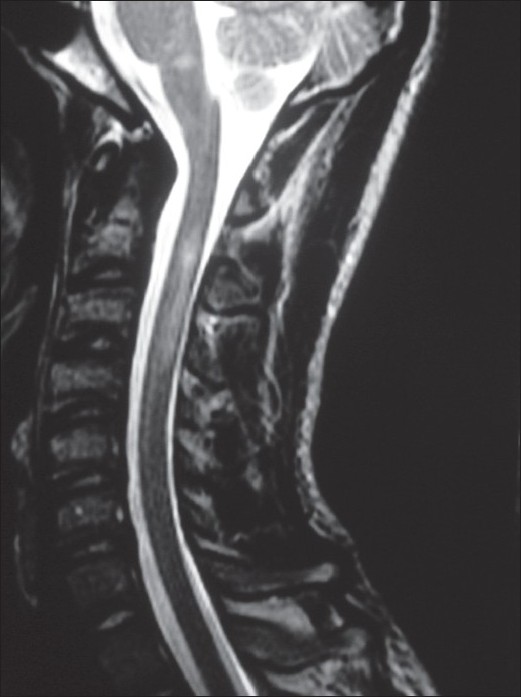

Ферменты печени аспартаттрансаминаза (AST; 232 МЕ / л) и аланина трансаминаза (ALT; 392 МЕ / л) были первоначально повышены и оседали несколько дней спустя. Обычная биохимия крови, включая остальные функции щитовидной железы, электрофорез сывороточного белка, уровень витамина В12 и фолата, были нормальными. Скрининговые тесты на наличие антиядерных антител, ревматоидного фактора, антинейтрофильных цитоплазматических антител (ANCA), криоглобулинов, C3, C4 и анти-аквапорин-4 были отрицательными. Микробиологический скрининг на наличие инфекции (сыворотка) был неопределенным для ВГС и отрицательным для остальных, включая вирус иммунодефицита человека (ВИЧ), гепатит В, цитомегаловирус (сыворотка), вирус простого герпеса, вирус опоясывающего лишая, трепонему паллидумную и микобактерии туберкулеза (сыворотка и спинномозговая жидкость). Анализ спинномозговой жидкости показал 594 мг / дл белков и 55 клеток / мл (преимущественно лимфоциты). Магнитно-резонансная томография (МРТ) головного и спинного мозга выявила множественные субкортикальные и перивентрикулярные повреждения белого вещества, гиперинтенсивность на T2-взвешенных изображениях и гипоинтенсивность в T1, некоторые из них усиливались усилением гадолиния (Gd) [Figure 1] . В шейном отделе спинного мозга наблюдались неусиливающиеся изменения интрамедуллярного сигнала, аналогичные поражениям головного мозга [Рисунок 2]., Электромиографическое исследование показало демиелинизирующую полиневропатию, которая при этом поступлении считалась острой. Он получал 5-дневный курс внутривенного введения иммуноглобулина (IVIg, 0,4 г / кг / день), а также был назначен преднизон (1 мг / кг / день). Он показал немедленное улучшение мышечной силы и других неврологических нарушений, которые были отмечены в течение следующих нескольких месяцев. В ходе наблюдения ранее неопределенная серология ВГС, а также полимеразная цепная реакция (ПЦР) на вирус ВГС были положительными.

Через шесть месяцев после первого приема у больной появились клинические признаки миелопатии: пирамидный квадрипарез и дисфункция мочевого пузыря. Повторное исследование CSF показало небольшое увеличение уровней клеток (23 клетки / мл, преимущественно лимфоцитов) и белка (78 мг / дл). Повторное МРТ шейки матки показало увеличение контрастности новых поражений, преимущественно в шейно-грудном сегменте. МРТ головного мозга показала улучшение предыдущих поражений головного мозга. Ему давали пульсирующее лечение кортикостероидами и вводили перорально преднизон по 20 мг / сут. Он показал постепенное выздоровление. Биопсия печени показала активное воспаление, и ему был назначен альфа-интерферон и кортикостероиды для лечения ВГС. Поскольку после одного месяца противовирусного лечения у него ухудшился неврологический дефицит, интерферон был остановлен.